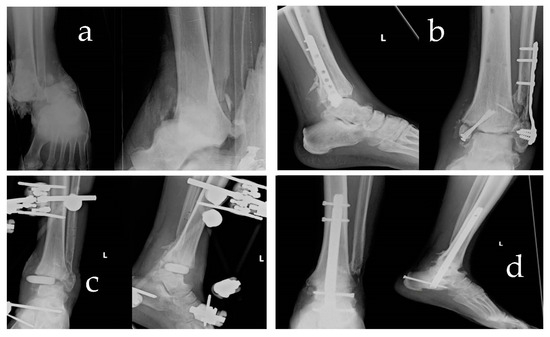

Overall, the results of our study demonstrate that retrograde nail arthrodesis is an effective treatment option for severe ankle fractures, leading to successful bone callus consolidation, consecutive ankle arthrodesis, and functional recovery. While complications were encountered, they have managed appropriately, and the overall outcomes were favourable. These findings support the use of this technique in cases where limb salvage is crucial and amputation is the alternative. (Figure 1)

Figure 1. Figure shows a clinical case examined. The image in (a) shows fracture dislocation type 44B3. The image in (b) shows clinical follow-up at 2 months with media exposure and staphylococcus aureus mrsa infection. (c) Control post debridement and curettage of devitalised tissue, removal of synthesis devices, stabilisation with external fixator, and implant of antibiotic spacer. (d) Clinical follow-up at 6 months of arthrodesis with retrograde nail and RIA graft.